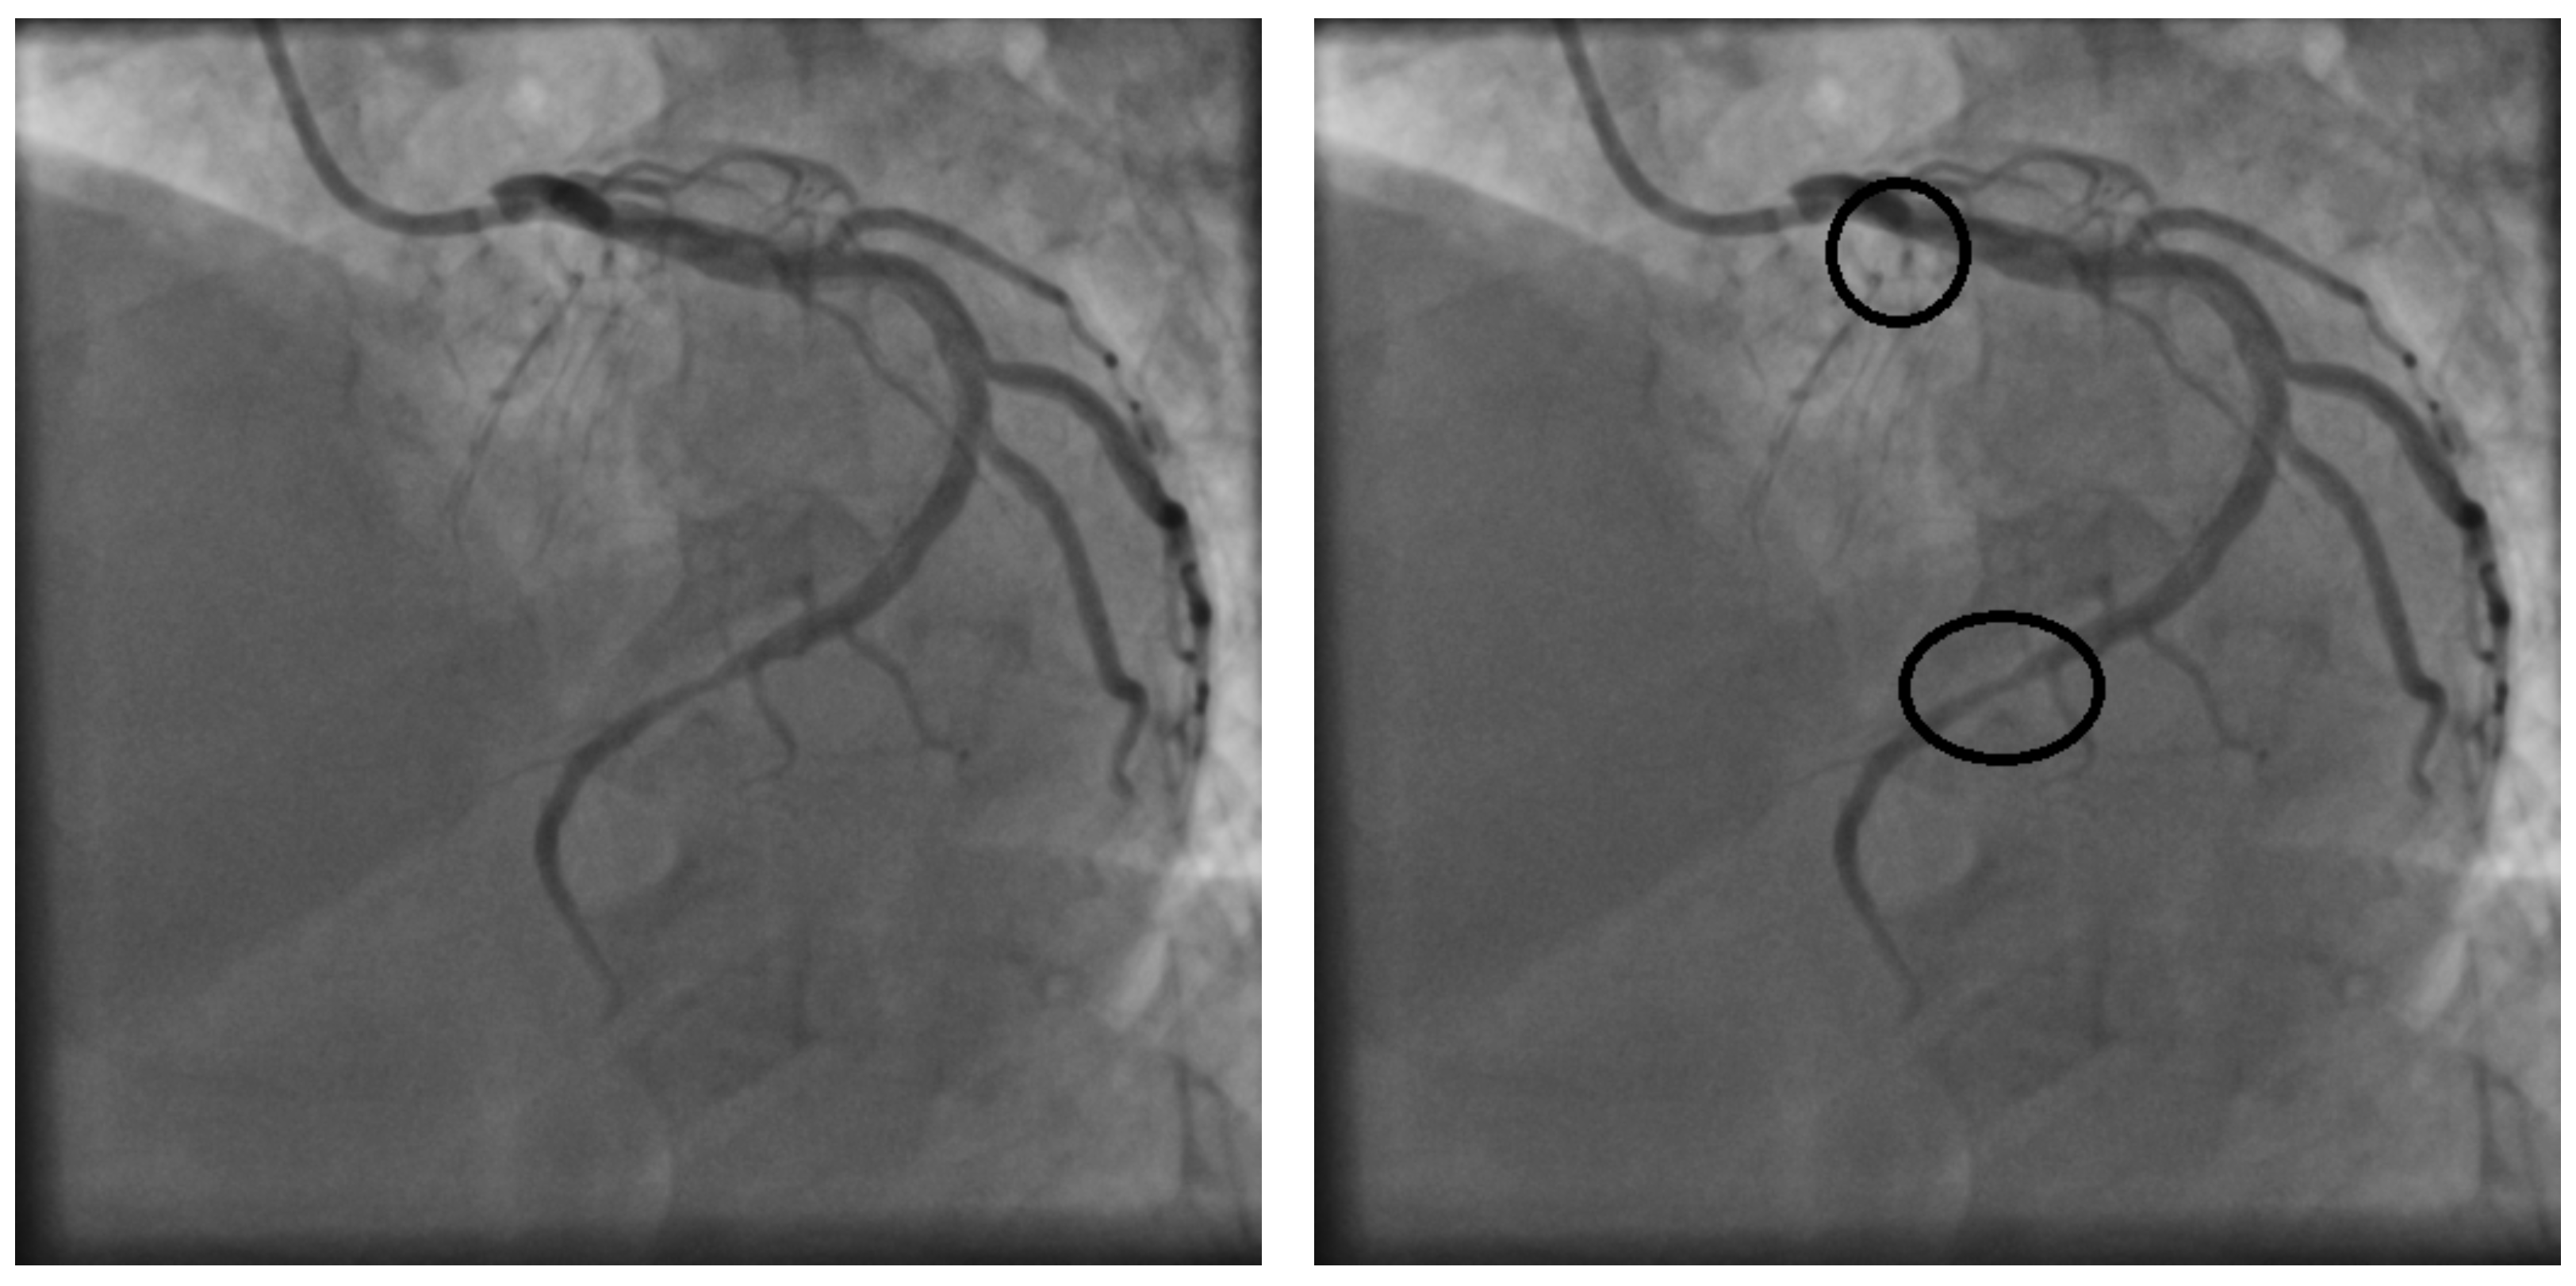

4.1. Image Database